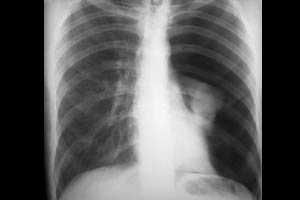

- Инструментальное обследование. При пневмонии рентгенография легких позволяет выявить очаги воспаления, которые визуализируются как участки затемнения. При разрывах легкого просматривается смещенное средостение, коллапс органа. Травмы дыхательных путей обнаруживаются при проведении бронхоскопии. Для уточнения диагноза используют компьютерную томографию пораженного участка.

Ателектаз при проведении ИВЛ может иметь свой причиной как неправильное стояние эндотрахеальной (трахеостомической) трубки — ее расположение в одном из главных бронхов (чаще в правом), так и закупорку главного или долевых бронхов сгустками мокроты. Все это приводит к гиповентиляции или полному отсутствию вентиляции перекрытых отделов бронхолегочного дерева. Ателектаз проявляется ослаблением дыхания над пораженным участком, а также характерной рентгенологической картиной. Лечение ателектаза заключается в устранении его причины и дальнейшем продолжении ИВЛ.

Вентилятор-ассоциированная пневмония является поздним осложнением механической вентиляции легких. Она обычно развивается начиная с третьи суток пребывания пациента на ИВЛ. Как правило, вентилятор-ассоциированная пневмония вызывается внутрибольничной флорой реанимационного отделения, а отсюда плохо поддается стандартной антибактериальной терапии. Наиболее частые возбудители: клиебсиелла, ацинетобактер, золотистый стафилококк. Диагностика вентилятор-ассоциированной пневмонии проводится на основании клиники (стойкая лихорадка, аускультативная картина), лабораторных данных, рентгенологической картины. Обязателен посев мокроты и определение чувствительности выделенной культуры к антибиотикам. Лечение заключается в назначении эмпирической, а затем и прицельной антибактериальной терапии, обычно состоящей из антибиотиков резерва. Эффективно также назначение антибиотиков и антисептических средств ингаляционно.